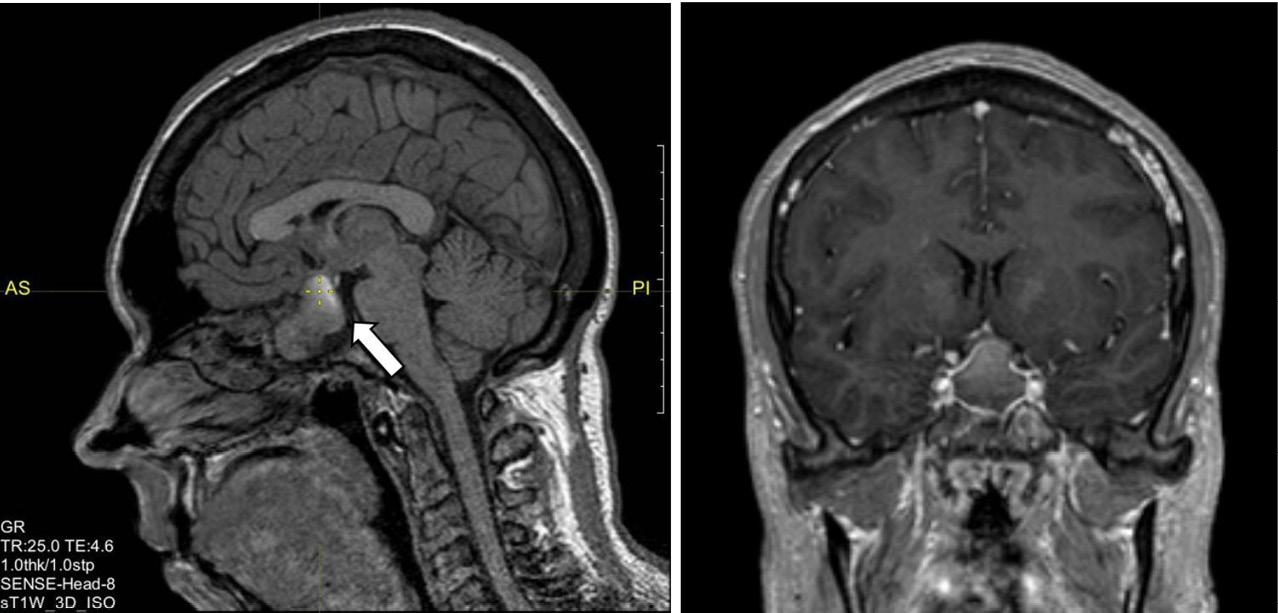

Женщина 42 лет 09.12.2020 была доставлена бригадой скорой медицинской помощи с подозрением на острое нарушение мозгового кровообращения в приемное отделение БУЗ УР «1 РКБ МЗ УР» с жалобами на сильную головную боль в лобной области, повышение артериального давления (АД) до 160/100 мм рт. ст., общую слабость, повышение температуры тела до 37,5 °C, по поводу чего принимала метамизол натрия без эффекта. По результатам компьютерной томографии головного мозга данных за острое нарушение мозгового кровообращения выявлено не было; обнаружена макроаденома гипофиза размерами 28 × 21 × 22 мм с интра-, инфраселлярным ростом, распространявшаяся из гипофизарной ямки через разрушенное дно турецкого седла в полость основной пазухи. По данным далее проведенной магнитно-резонансной томографии (МРТ) гипофиза с контрастированием подтверждена макроаденома гипофиза размерами 22 × 32 × 23 мм с супра-, инфра-, латероселлярным ростом с компрессией воронки гипофиза, хиазмы зрительных нервов слева, охватом внутренней сонной артерии с двух сторон (рис. 1). Гормональное исследование от 12.01.2021: ИФР-1 – 49,8 нг/мл (43–209)1 [1]. При компьютерной сферопериметрии выявлены единичные периферические относительные скотомы, абсолютные скотомы правого глаза и рассеянные относительные скотомы левого глаза.

Рис. 1. Магнитно-резонансная томография гипофиза с контрастным усилением, Т1-взвешенные изображения. Визуализируется макроаденома гипофиза с супра-, инфра-, латероселлярным ростом с кровоизлиянием (указана стрелкой)

В феврале 2021 г. находилась на госпитализации в ГНЦ РФ ФГБУ «НМИЦ эндокринологии» Минздрава России. Верифицирован диагноз акромегалии по данным СТГ > 1 нг/мл в ходе ОГТТ (см. табл. 1) и с учетом характерной клинической симптоматики при нормальном уровне ИФР-1 – 202,4 нг/мл (51–271). По данным МРТ от 17.02.2021 визуализирована аденома гипофиза с кровоизлиянием размерами 16,5 × 20 × 23 мм с супра-, инфра-, антеселлярным ростом, размеры которой уменьшились по сравнению с результатом от декабря 2020 г. Пациентка консультирована нейрохирургом – рекомендовано трансназальное нейрохирургическое лечение. Одновременно был подтвержден папиллярный рак щитовидной железы с метастазами в региональные лимфоузлы. Первым этапом лечения рекомендовано проведение хирургического лечения папиллярного рака щитовидной железы. В связи с нецелевыми значениями св. Т4 на фоне приема 75 мкг левотироксина (св. Т4 13,55 пмоль/л (9–19)) доза препарата была увеличена до 100 мкг в сутки.